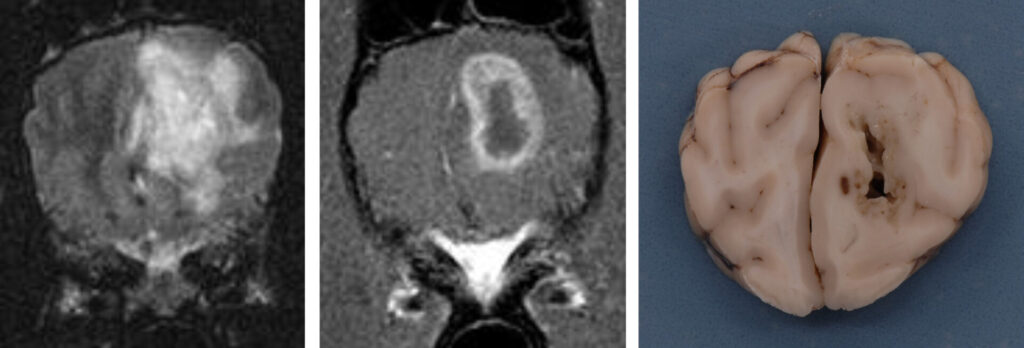

In order to diagnose brain tumours, CT-scans or MRI-scans are used to image the brain. Despite the fact that these tests are very good at detecting the presence of a mass in the brain, they are very poor at identifying its exact nature (i.e. whether it is a tumour, inflammation, or bleeding within the brain).

When it comes to people, a biopsy of a brain tumour is the preferred way to determine the type of tumour and other information regarding treatment and prognosis. Normally, we do not recommend brain biopsy in animals since it is a very invasive and potentially risky procedure. A veterinary neurologist will often diagnose a tumour type based on key features on scans. This approach has limitations, so it is difficult to provide accurate information regarding treatment and prognosis.

• Surgery: Surgically removing the tumour completely is the ultimate goal of cancer surgery. It is rare for this to be possible with brain tumours, and nearly always tumour cells are left behind, causing them to grow back. By removing the bulk of the tumour, other treatments may have a better chance of success; the remaining cells may become more ‘sensitive’ to radiation after removal of the bulk of the tumour during surgery. Most brain tumours in humans are treated with polytherapy (a combination of medication, surgery, and radiation). As a result of surgery, it may be possible to obtain a sample of the mass and identify its nature. This will allow a more accurate prediction of the patient’s future. It is not possible to remove all brain tumours in dogs and cats surgically; surgical feasibility depends on where in the brain the tumour is located. On the surface of the brain, tumours are more likely to be removal via surgery. A surgeon would have to cut through a large area of healthy brain tissue in order to reach a tumour deep within the brain. This could have disastrous consequences for the patient’s recovery. There are several options for treatment, but surgery is the most invasive and costly. Brain surgery can sometimes result in irreversible damage to the brain, although many dogs recover well without complications. It has been reported that some owners have noticed a change in their pet’s personality and behaviour following surgery. Surgery on the brain involves risks, especially if the patient has other health issues, since it requires a lengthy anaesthetic. There are times when a patient may not recover from surgery. Choosing this option may provide a pet with the longest period of quality of life although the associated risks must be considered. With few exceptions, veterinary neurologists do not recommend surgery for deep-seated brain tumours because it can cause more harm than benefit. Meningiomas or some tumours of the pituitary gland can, however, be surgically treated, often with good results.